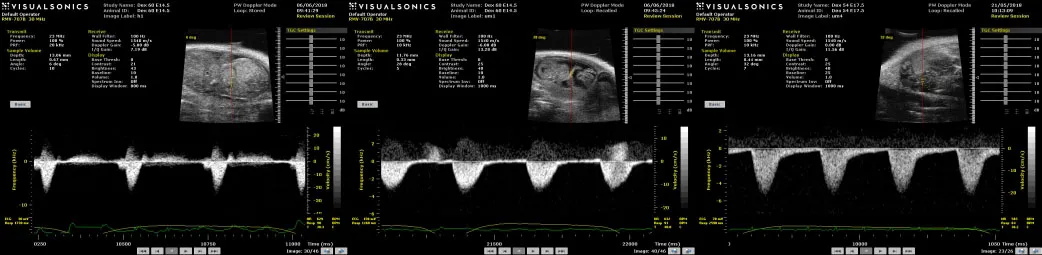

Heterozygous glucocorticoid receptor (GR) knockout mice are being used to investigate the role of endogenous glucocorticoids in placental vascularisation and hemodynamics. Heterozygous matings produce offspring with normal, haploinsufficient or absent GR-mediated glucocorticoid action. To simulate clinical administration of exogenous glucocorticoids, pregnant C57BL/6 mice receive an IP injection of vehicle or dexamethasone (500μg/kg) at gestational day [E] 13.5 or E16.5, with analysis of placental and fetal parameters 24h later. In both experiments, in vivo

pre-clinical ultrasound scanning is conducted in separate cohorts, at E14.5 or E17.5, to measure umbilical arterial blood flow (a key regulator of fetal and placental growth) and fetal heart function. Future experiments will analyse placental morphology and molecular pathways to develop a comprehensive understanding of how these parameters translate to hemodynamic function of glucocorticoid-exposed placentas.

visual sonics graph and key